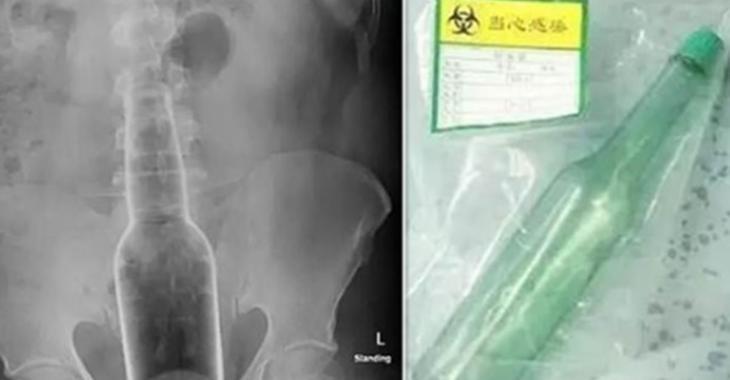

Une vérification aux rayons X a révélé que l'article était une bouteille.

Lors d'un examen physique, le Dr Lin a détecté un objet dur logé dans le rectum de M. Wen à quelques centimètres de son anus.

Le Dr Lin a pratiqué la chirurgie immédiatement afin d'extraire l'objet du patient et l'opération s'est déroulée avec succès.